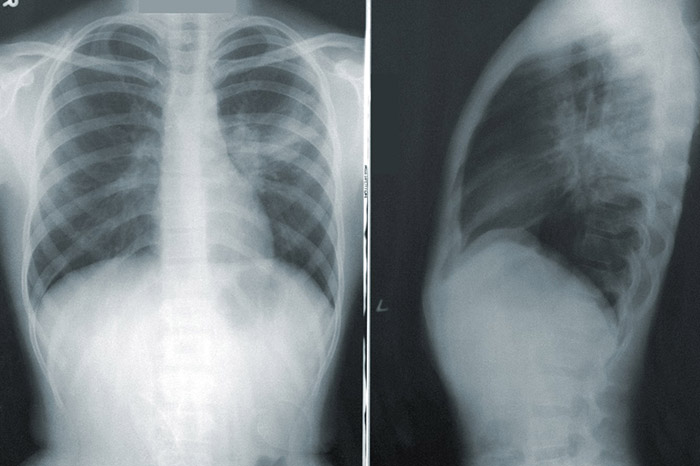

Пневмония может быть осложнением при коронавирусе, если инфекция протекает в тяжелой форме. Иногда пневмонию удается выявить раньше, чем коронавирус, вызвавший ее.